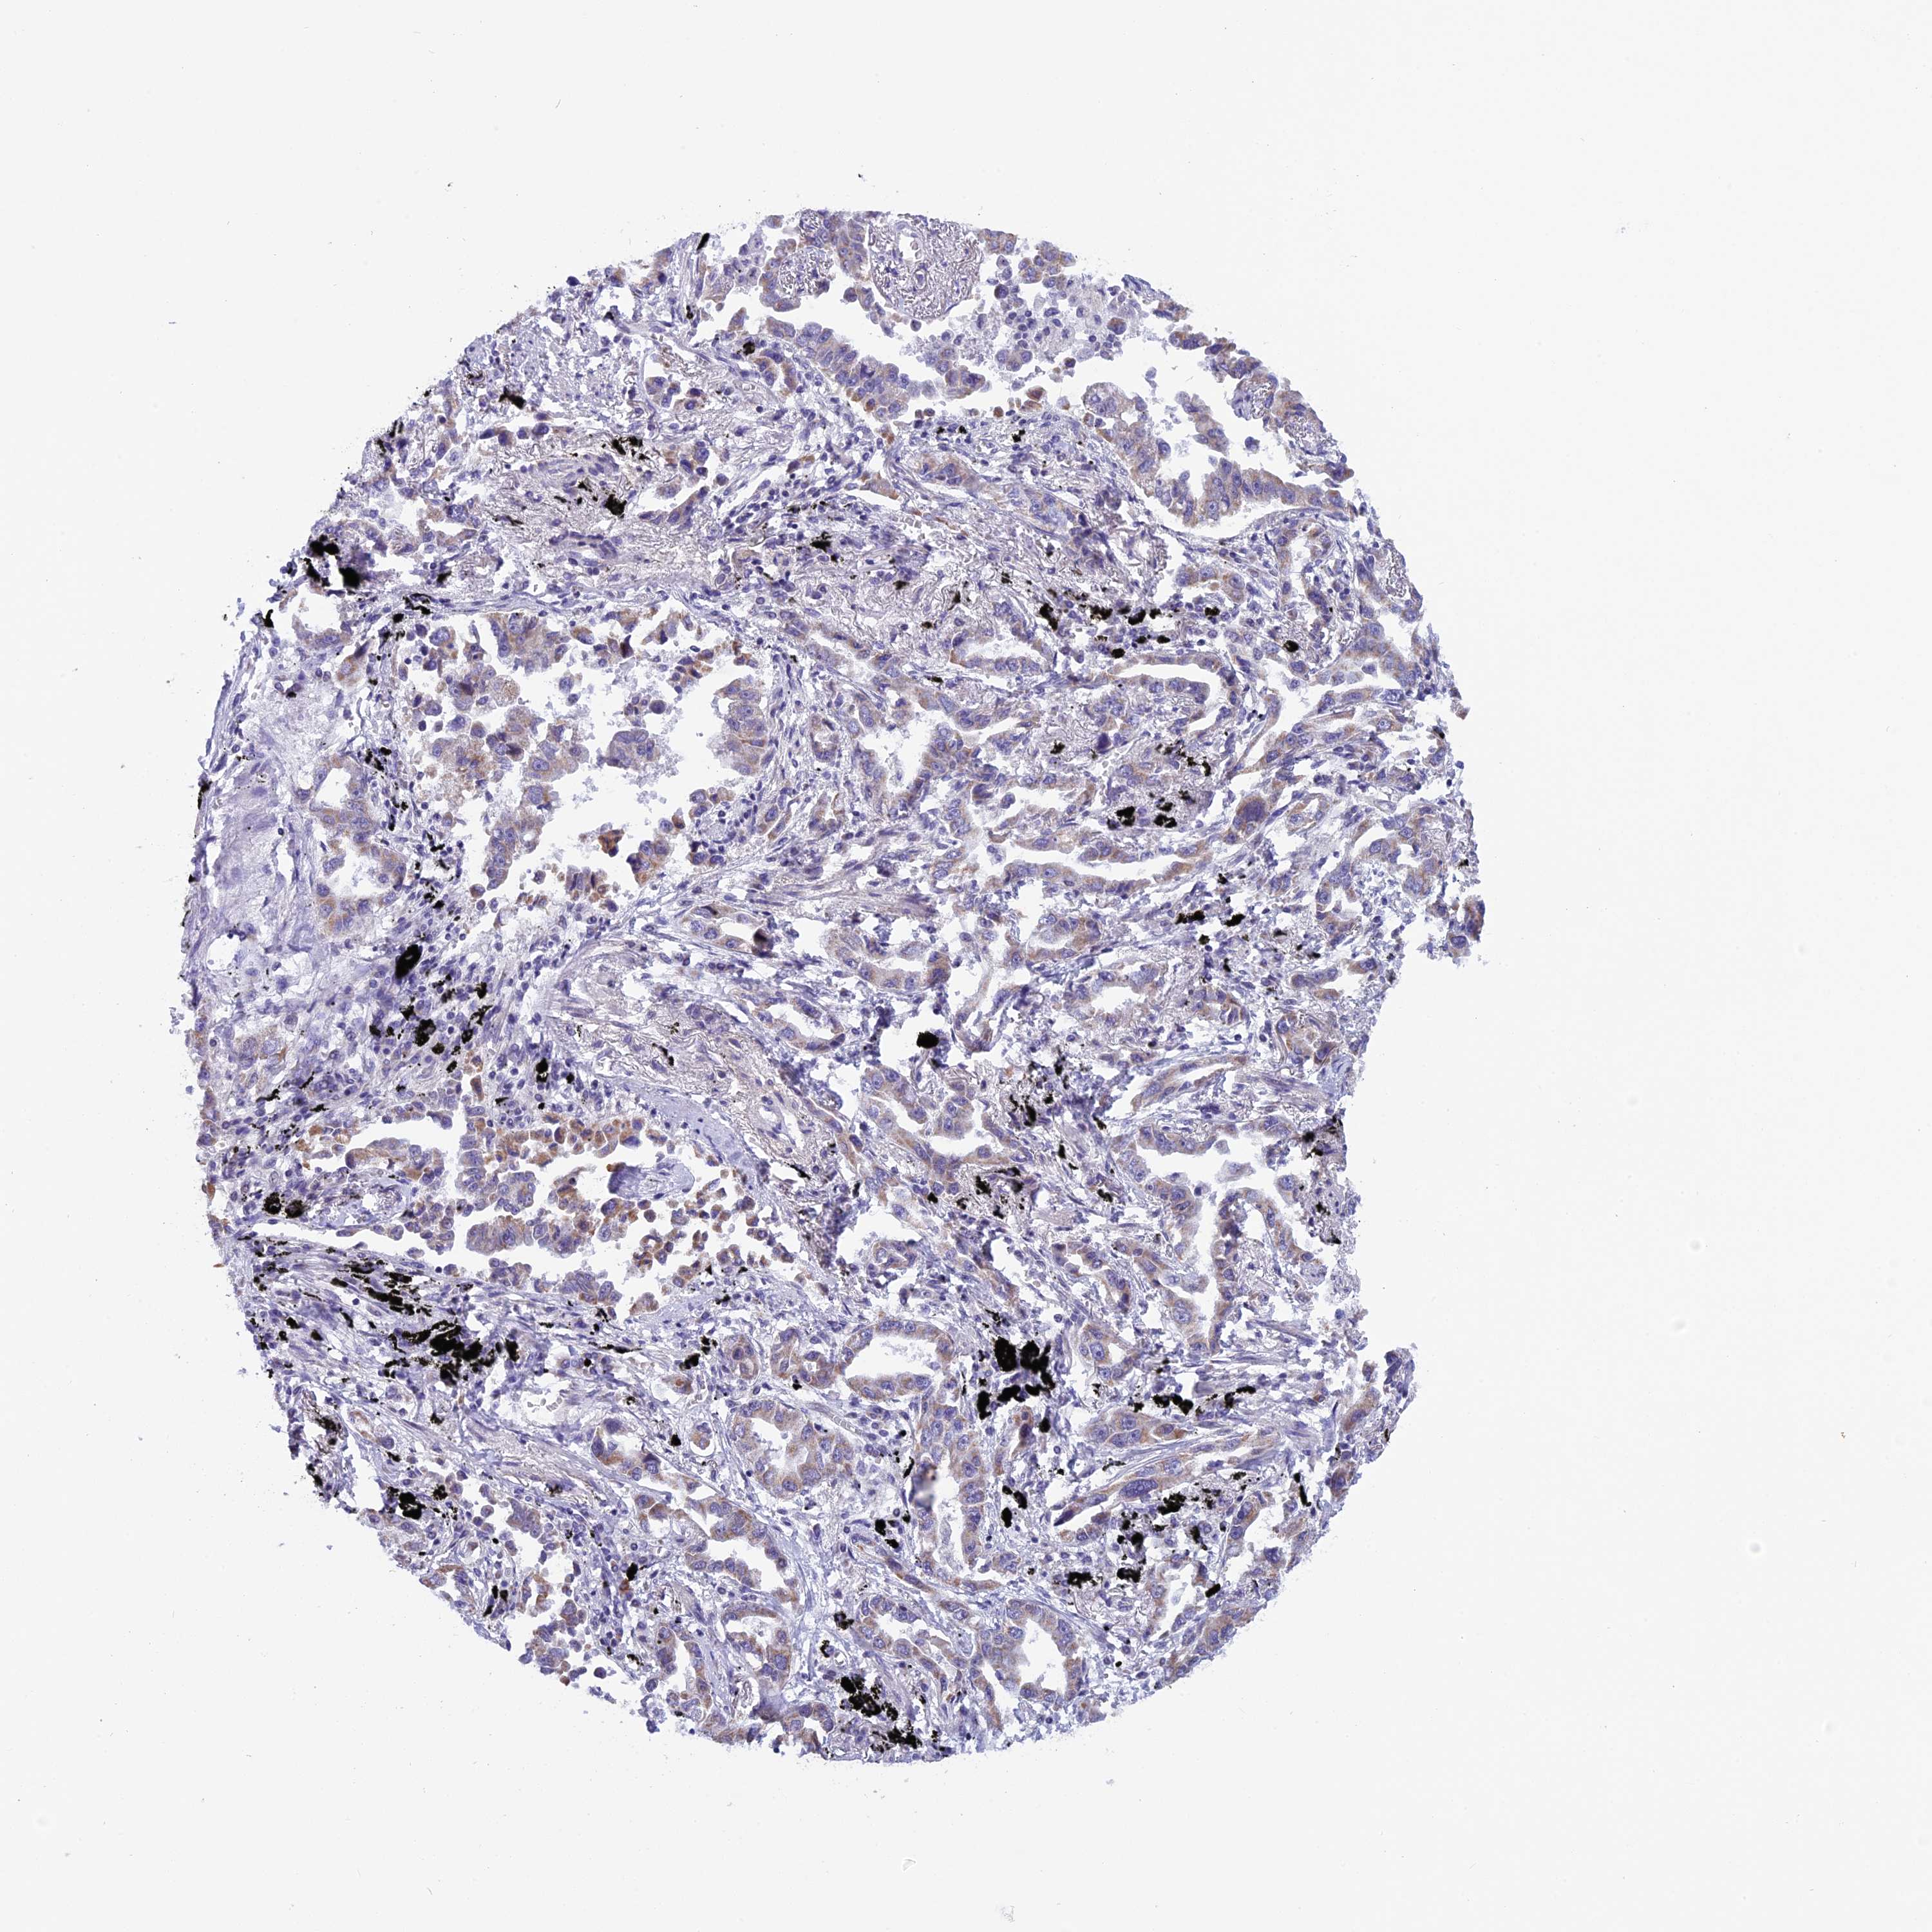

LUNG SQUAMOUS CELL CARCINOMA (TCGA) - Interactive survival scatter ploti

The Survival Scatter plot shows the clinical status (i.e. dead or alive) for all individuals in the patient cohort, based on the same data that underlies the corresponding Kaplan-Meier plots. Patients that are alive at last time for follow-up are shown in blue and patients who have died during the study are shown in red.

The x-axis shows the expression levels (FPKM) of the investigated gene in the tumor tissue at the time of diagnosis. The y-axis shows the follow-up time after diagnosis (years). Both axes are complimented with kernel density curves demonstrating the data density over the axes. The top density plot shows the expression levels (FPKM) distribution among dead (red) and alive patients (blue). The right density plot shows the data density of the survived years of dead patients with high and low expression levels respectively, stratified using the cutoff indicated by the vertical dashed line through the Survival Scatter plot. This cutoff is automatically defined based on the FPKM cutoff that minimizes the p-score. The cutoff can be changed by dragging the vertical line or by entering a cutoff value in the square labeled "Current cut-off".

Under the Survival Scatter plot the p-score landscape (black curve; left axis) is shown together with dead median separation (red curve; right axis). Dead median separation is the difference in median mRNA expression between patients who have died with high and low expression, respectively. It is calculated as follows: median FPKM expression of dead patients with high expression - median FPKM expression of dead patients with low expression. This is intended to aid the user in visually exploring custom cutoffs and the associated p-scores and dead median separation.

Individual patient data is displayed and can be filtered by clicking on one or more of the category buttons on the top of the page. Categories describing expression level and patient information include: high, low, alive, dead, female, male and tumor stages. The scale of the x-axis can be toggled between linear and log-scale by clicking on the "x log" button. Mouse-over function shows TCGA ID, patient information and mRNA expression (FPKM) for each patient.

& Survival analysisi

Kaplan-Meier plots summarize results from analysis of correlation between mRNA expression level and patient survival. Patients were divided based on level of expression into one of the two groups "low" (under cut off) or "high" (over cut off). X-axis shows time for survival (years) and y-axis shows the probability of survival, where 1.0 corresponds to 100 percent.

ZNF317 is not prognostic in Lung Squamous Cell Carcinoma (TCGA)

Best expression cut offi

Based on the FPKM value of each gene, patients were classified into two groups and association between prognosis (survival) and gene expression (FPKM) was examined. The best expression cut-off refers the FPKM value that yields maximal difference with regard to survival between the two groups at the lowest log-rank P-value. Best expression cut-off was selected based on survival analysis .

When clicking on this number, the vertical dashed line indicating cut-off, the interactive survival plot, and the Kaplan-Meier curve will be adjusted to show results based on the best expression cut-off.

: 10.42

P scorei

Log-rank P value for Kaplan-Meier plot showing results from analysis of correlation between mRNA expression level and patient survival.

N/A

TCGA RNA samplesi

RNA-seq data is reported as average FPKM (number Fragments Per Kilobase of exon per Million reads), generated by the The Cancer Genome Atlas (TCGA) .

Normal distribution across the dataset is visualized with box plots, shown as median and 25th and 75th percentiles. Points are displayed as outliers if they are above or below 1.5 times the interquartile range. FPKM values of the individual samples are presented next to the box plot.

Average pTPM 15.4

Number of samples 489